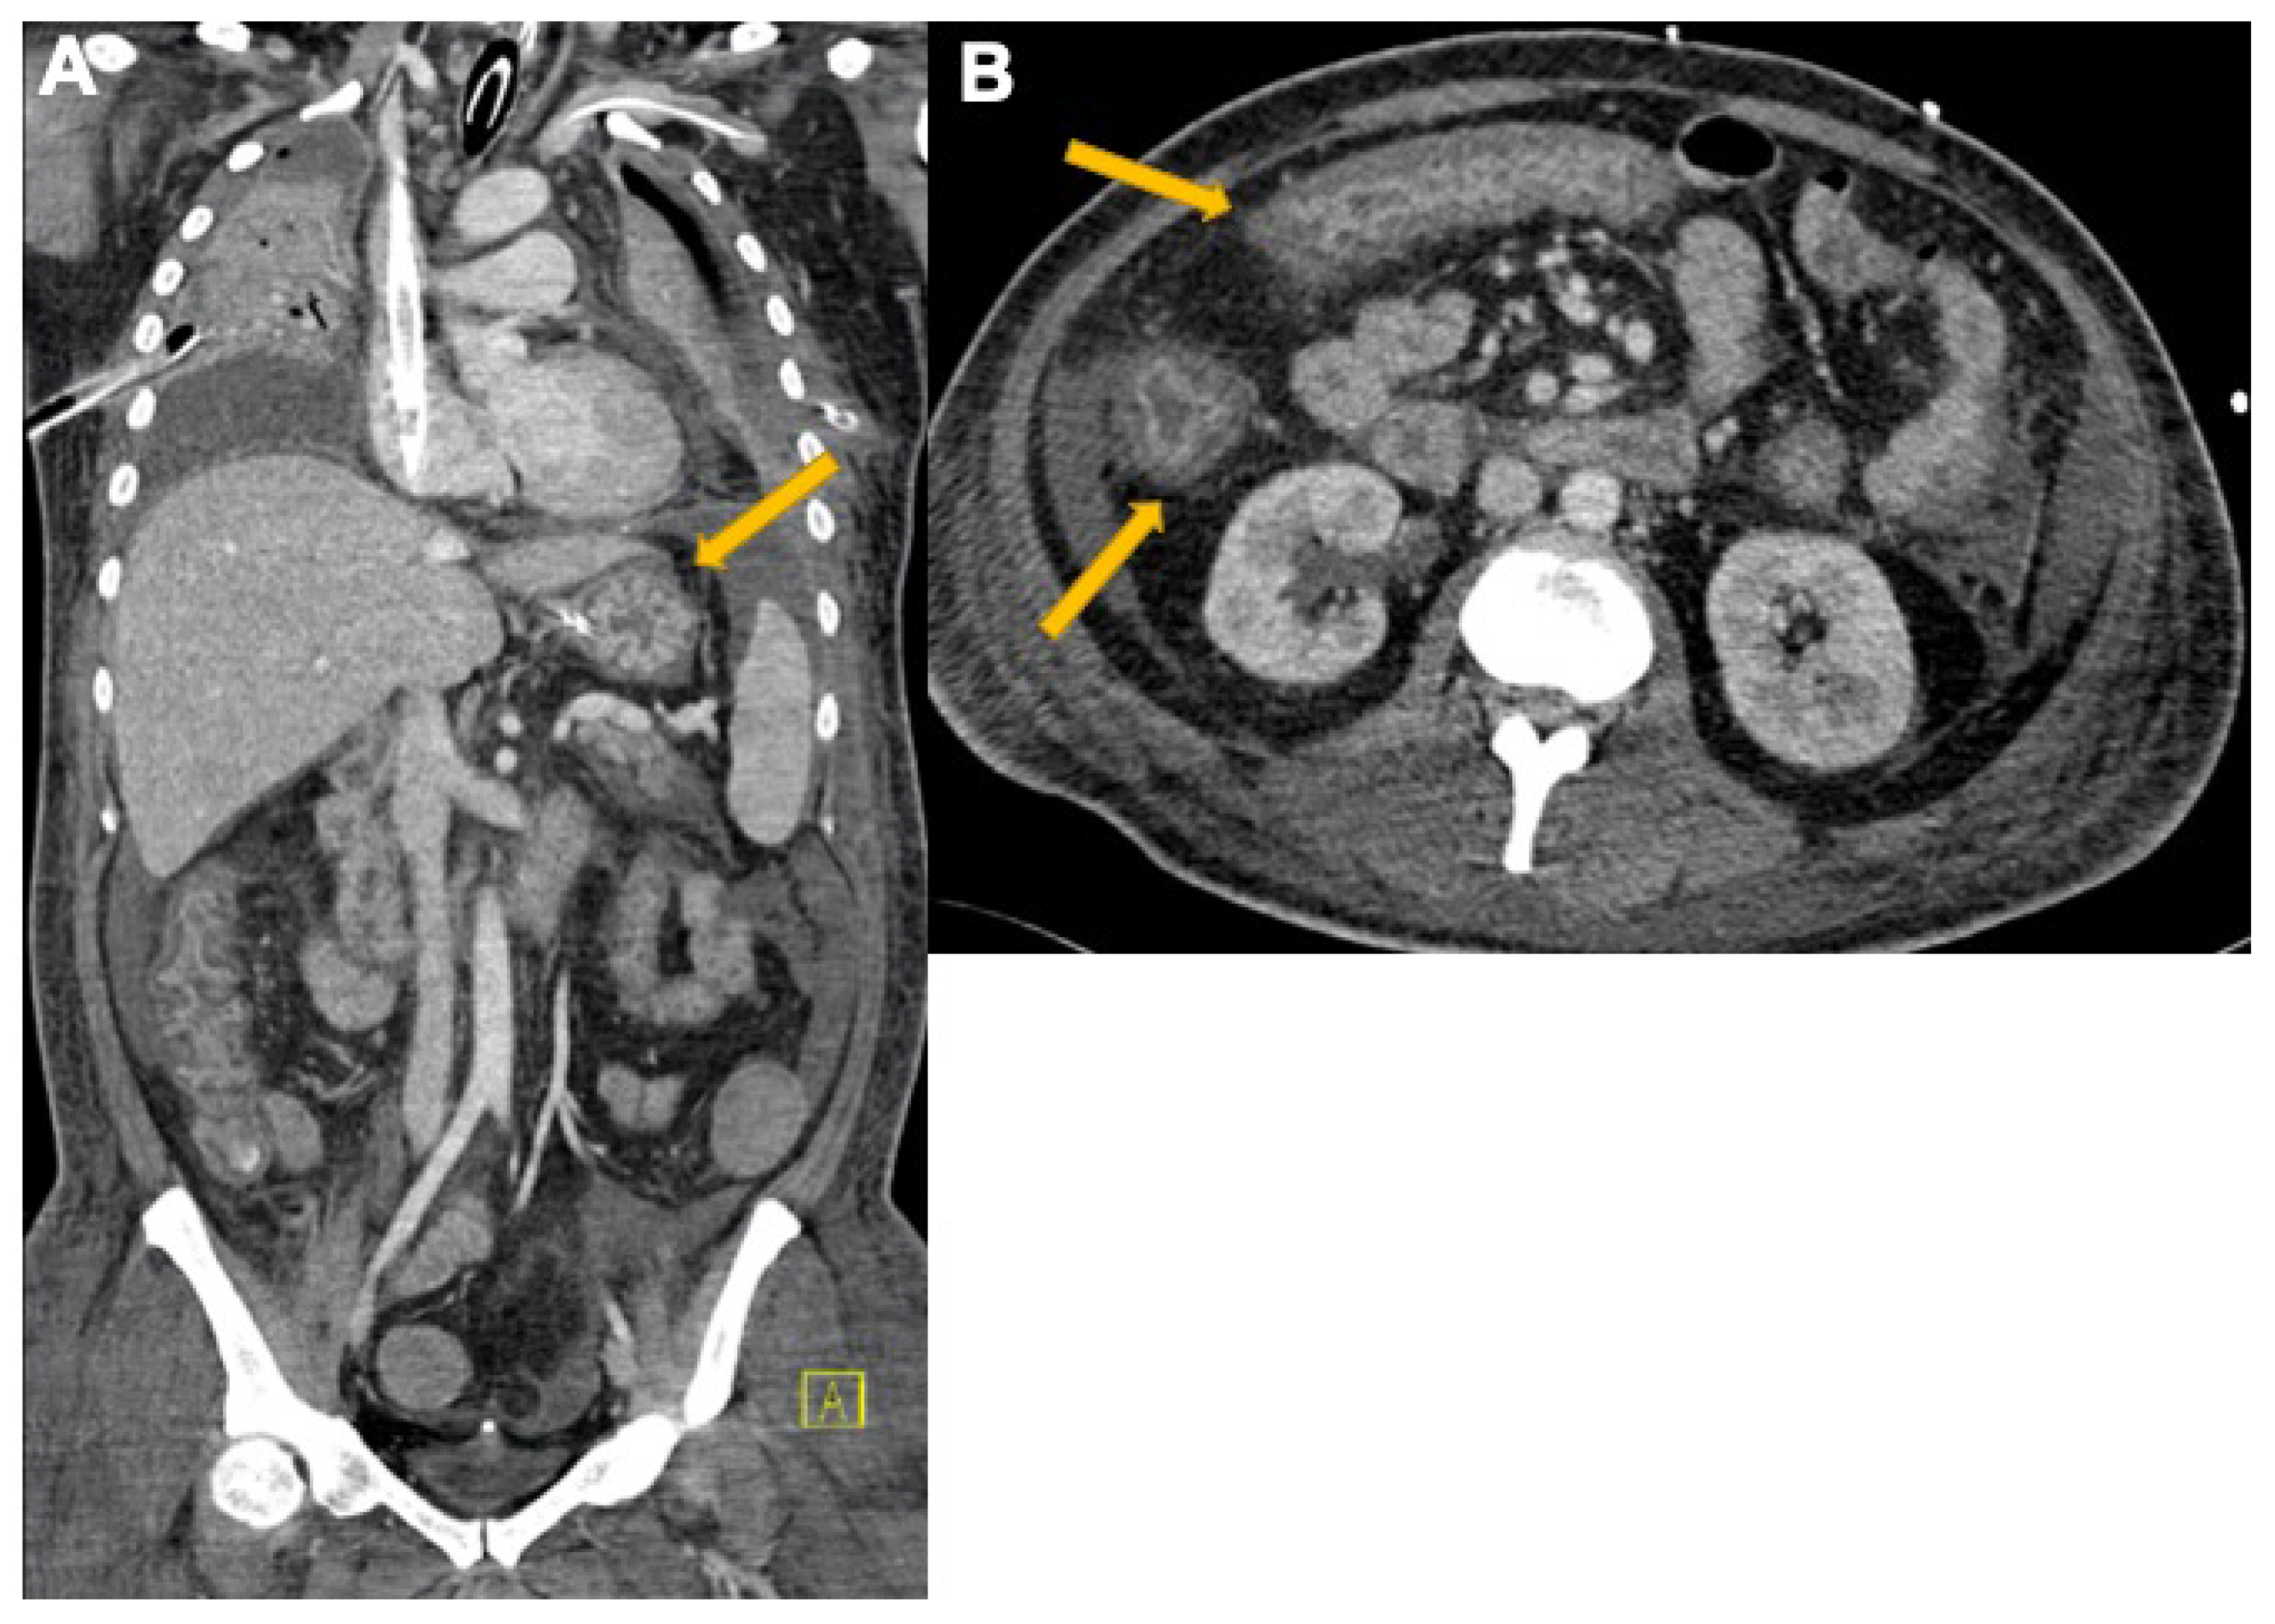

3.3. Abdominal Manifestations